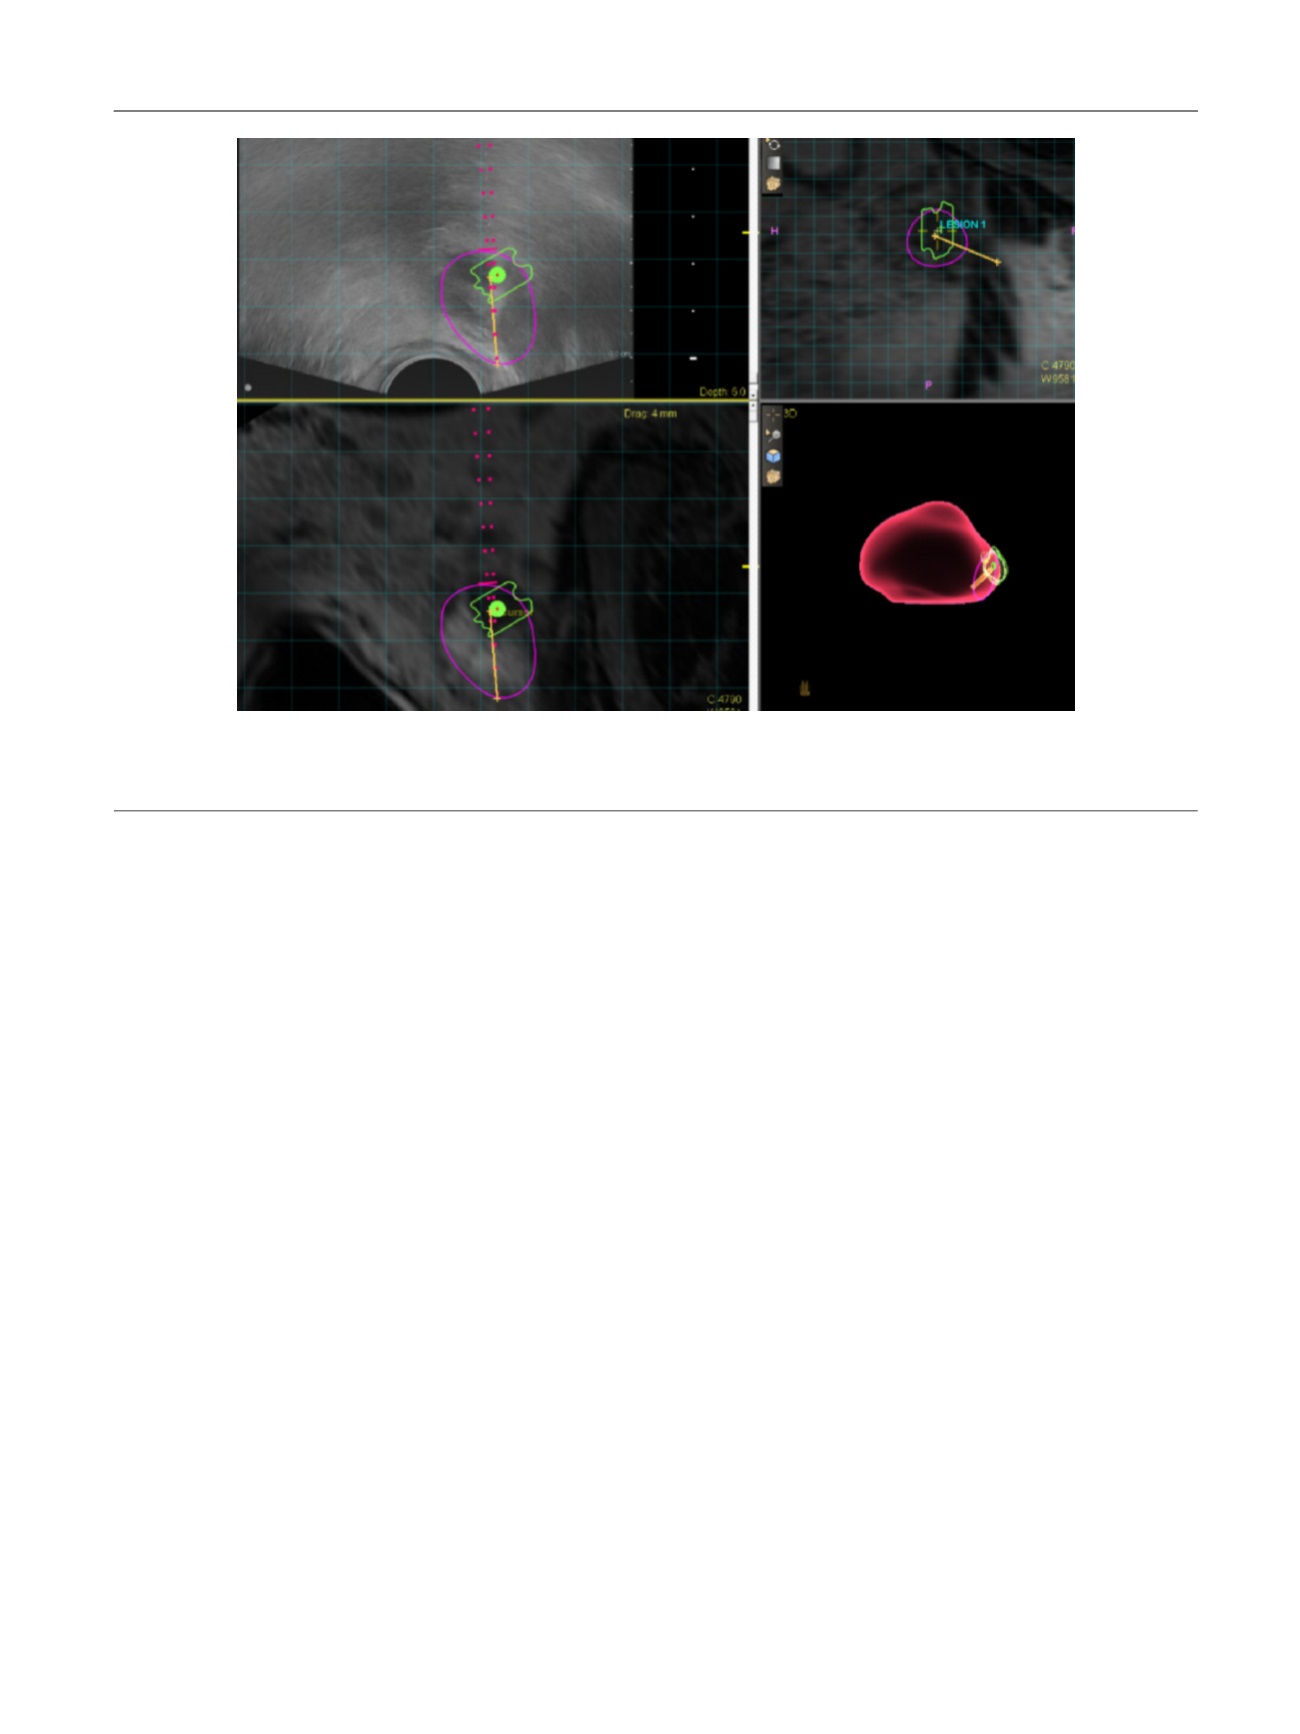

[(Fig._2)TD$FIG]

Fig. 2 – Representative screen capture of magnetic resonance imaging–ultrasound fusion biopsy in a 64-yr-old man with active surveillance for Gleason

score 3 + 3 disease. This specific lesion received a score of 5 on Prostate Imaging Reporting and Data System version 2 (highly likely to be clinically

significant cancer) with extracapsular extension, and targeted biopsy detected Gleason score 4 + 4 prostate cancer.